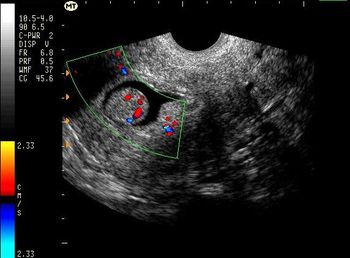

Gynecology Images: Normal Abnormal Obstetric Images: 1st Trimester: Normal Abnormal 2nd Trimester: Normal Abnormal 3rd Trimester: Normal Abnormal Medical Professionals: Upload Your Here Obstetric Images: 3rd Trimester: Normal Normal Thymus - Albana Cerekja Fetal urethra at 31 weeks: just before micturition - Albana Cerekja Normal Female: 4D still image - Effendi Mansoor Monolateral double renal artery,: Normal variant kidney artery supply - Albana Cerekja TRV Fetal Head: BPD and HC Measurements - SIEMENS Velamentosa insertion: 3rd trimester - Effendi Mansoor Umbilical Cord (3D Surface Rendering): Normal Cord - MEDISON SAG Fetal Face, Profile: Fetal Breathing on Color Doppler - SIEMENS 3D Surface Reconstruction: Face - Cayrol Guillermo 3D Surface Reconstruction: Extended Breech Presentation - Saied Mohamed Tohamy 3D Surface Reconstruction: Face - Juan Carlos Pons 3D Surface Reconstruction: Face and Foot - Cayrol Guillermo 3D Surface Reconstruction: Face - Juan Carlos Pons 3D Surface Reconstruction: Face - Juan Carlos Pons